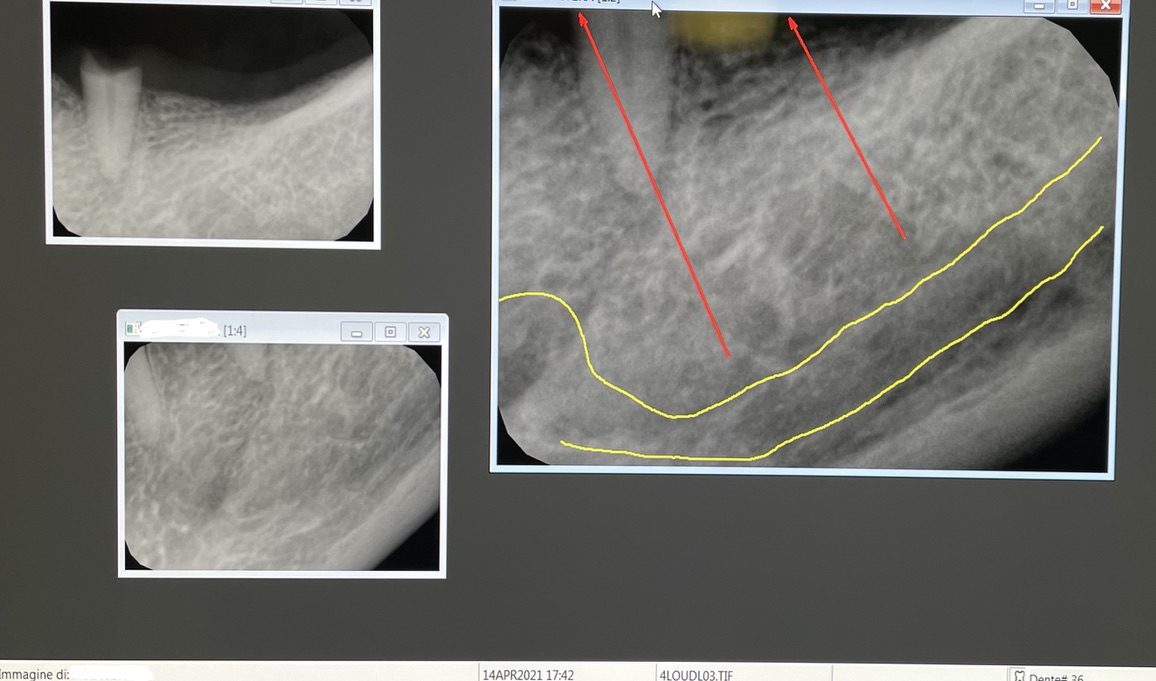

1 - AN INCISIVE CASE

Fracture of lower incisor element 31 and implant rehabilitation